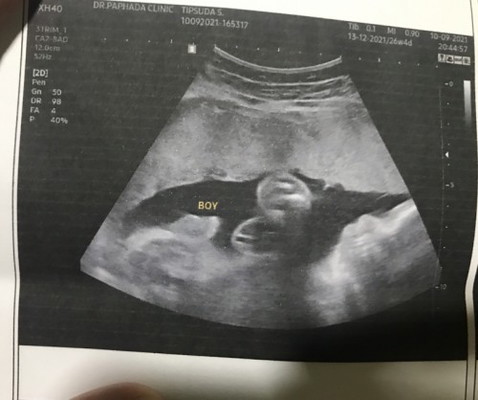

ชาย หรือ หญิง

มองยังไงให้เป็นจู๋คะ 🤣🤣 ชายจริงๆใช่ไหมคะแม่ แม่มองไม่ออกเลย อันนี้คือส่วนของลูกอัณฑะใช่มั้ยคะแม่ๆ สามีอยากได้ลูกสาว อิแม่อยากได้ลูกชาย ซาวด์ ตอน 26+3

น้องมีไส้กรอกกับไข่ดาวค่ะแม่ ดูตรงคำว่าBOYค่ะ ไส้กรอกน้องพับอยู่☺️

ไข่2ฟองของน้องค่าาา ^^

ไข่ชัดเลยจ้าแม่😁